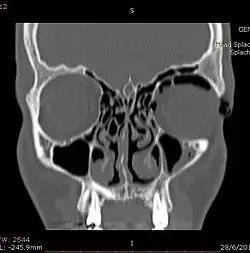

Computed tomography (CT)

Computed tomography is effective and sensitive in the diagnosis of orbital emphysema,[3][37] as it can confirm the anatomical location and size of air, bony defects, indentation of the eyeball, and the condition of the optic nerve, as well as the presence of any extraocular muscle entrapment and herniation of preorbital fat into the sinus cavities.[3][15][38] The location of the orbital emphysema is present near the site of the fracture.[1][3] The scans are usually taken along the transverse plane. Transverse images allow the evaluation of fractures in medial and lateral orbital walls. By reformatting these transverse images or taking coronal images, the examination of orbital floor and roof is permitted. Helical scanning is preferred as it has a lower imaging time and radiation dose comparing to conventional scanning, especially when reforming transverse helical scans into coronal images.[3] The staging of orbital emphysema can then be determined with visual acuity examination and ophthalmoscopy.[6] A disadvantage of using a CT scan is that when detecting air after orbital trauma, the presence of a wooden foreign object can give a false positive result of orbital emphysema. The wooden object can mimic the presence of orbital emphysema. Therefore, patients’ medical history is crucial in making the correct diagnosis.[3]